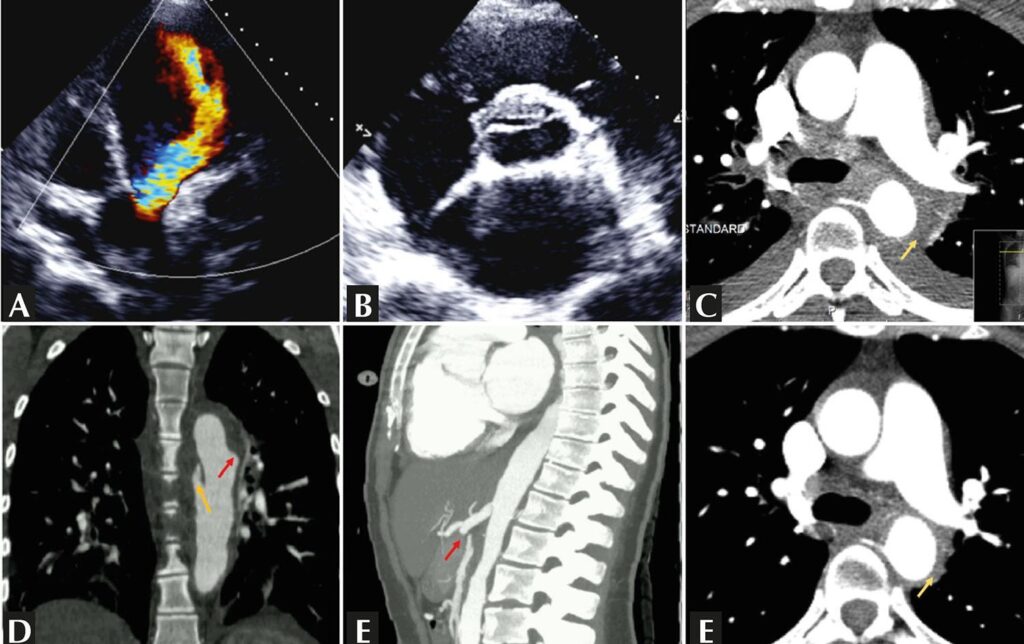

A 21-year-old woman was admitted with heart failure and chest pain. Echocardiography revealed a tricuspid aortic valve with severe regurgitation (A), a thickened and deformed right coronary cusp with a linear image (B), and severe left ventricular dilation. Angio-computed tomography showed continuous and concentric thickening of the aortic wall (C) with a penetrating ulcer and dissection of the descending aorta (D) and superior mesenteric and left renal arterial occlusion (E). Takayasu aortitis type V was assumed for which immunosuppression was commenced. Significant improvement was noted (F). After achieving remission, the patient underwent endovascular surgery of the aorta and aortic valve replacement. No episodes of relapses were seen during a 3-year follow-up period.